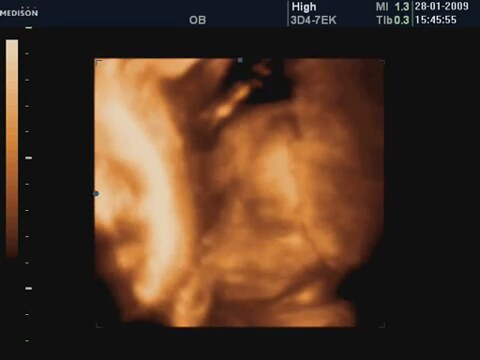

24 Haftalık Bebeğin 4 Boyutlu Ultrason Görüntüsü